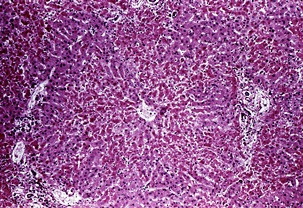

황달이란? (jaundice)

몸에 필요한 황색의 담즙색소 (빌리루빈)이 과도하게 쌓여 눈동자나 피부 등에 착색되는 현상을 말한다고 합니다. 이 담즙색소는 체내에 들어온 물질들이 분해되는 과정에서 생성되는 필요 없는 물질인데요. 일반적으로는 간에서 해독작용을 거친 후에 담즙으로 배설이 되는 것이 정상적이지만, 그렇지 못한 경우 황달이 발생하게 된다고 합니다.

황달이 생기는 이유는 담즙색소라고 알려진 빌리루빈이 과도하게 생기기 때문입니다. 빌리루빈은 우리 몸의 오래된 적혈구가 파괴되면서 생기는 물질인데요. 이 물질은 담즙에 녹아서 우리 몸의 배설물과 함께 배출이 되는 것이 정상적이지만 빌리루빈의 과잉생산이나, 간의 장애, 간세포나 담도의 손상에 의해 빌리루빈이 역류할 경우 발생된다고 합니다.